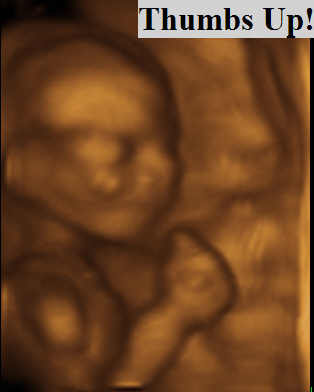

The Differences Between 2d 3d And 4d Ultrasounds Explained